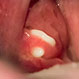

Thrush (Oral Candidiasis)

Thrush is an infection of the mouth caused by the Candida fungus. Symptoms of thrush include pain or difficulty swallowing, a feeling that food gets stuck in the throat, and fever.